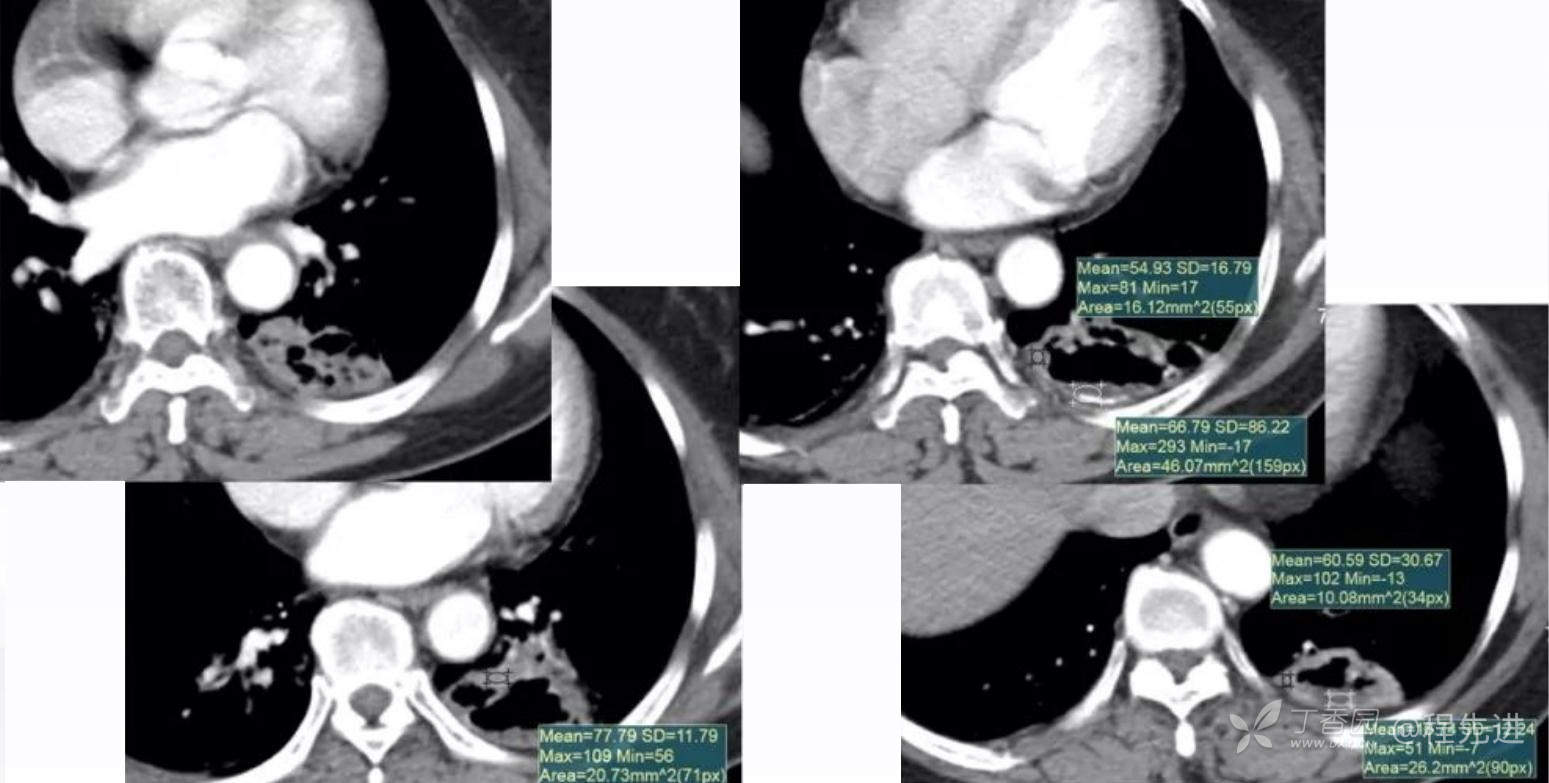

纵隔窗平扫

增强动脉期

静脉期